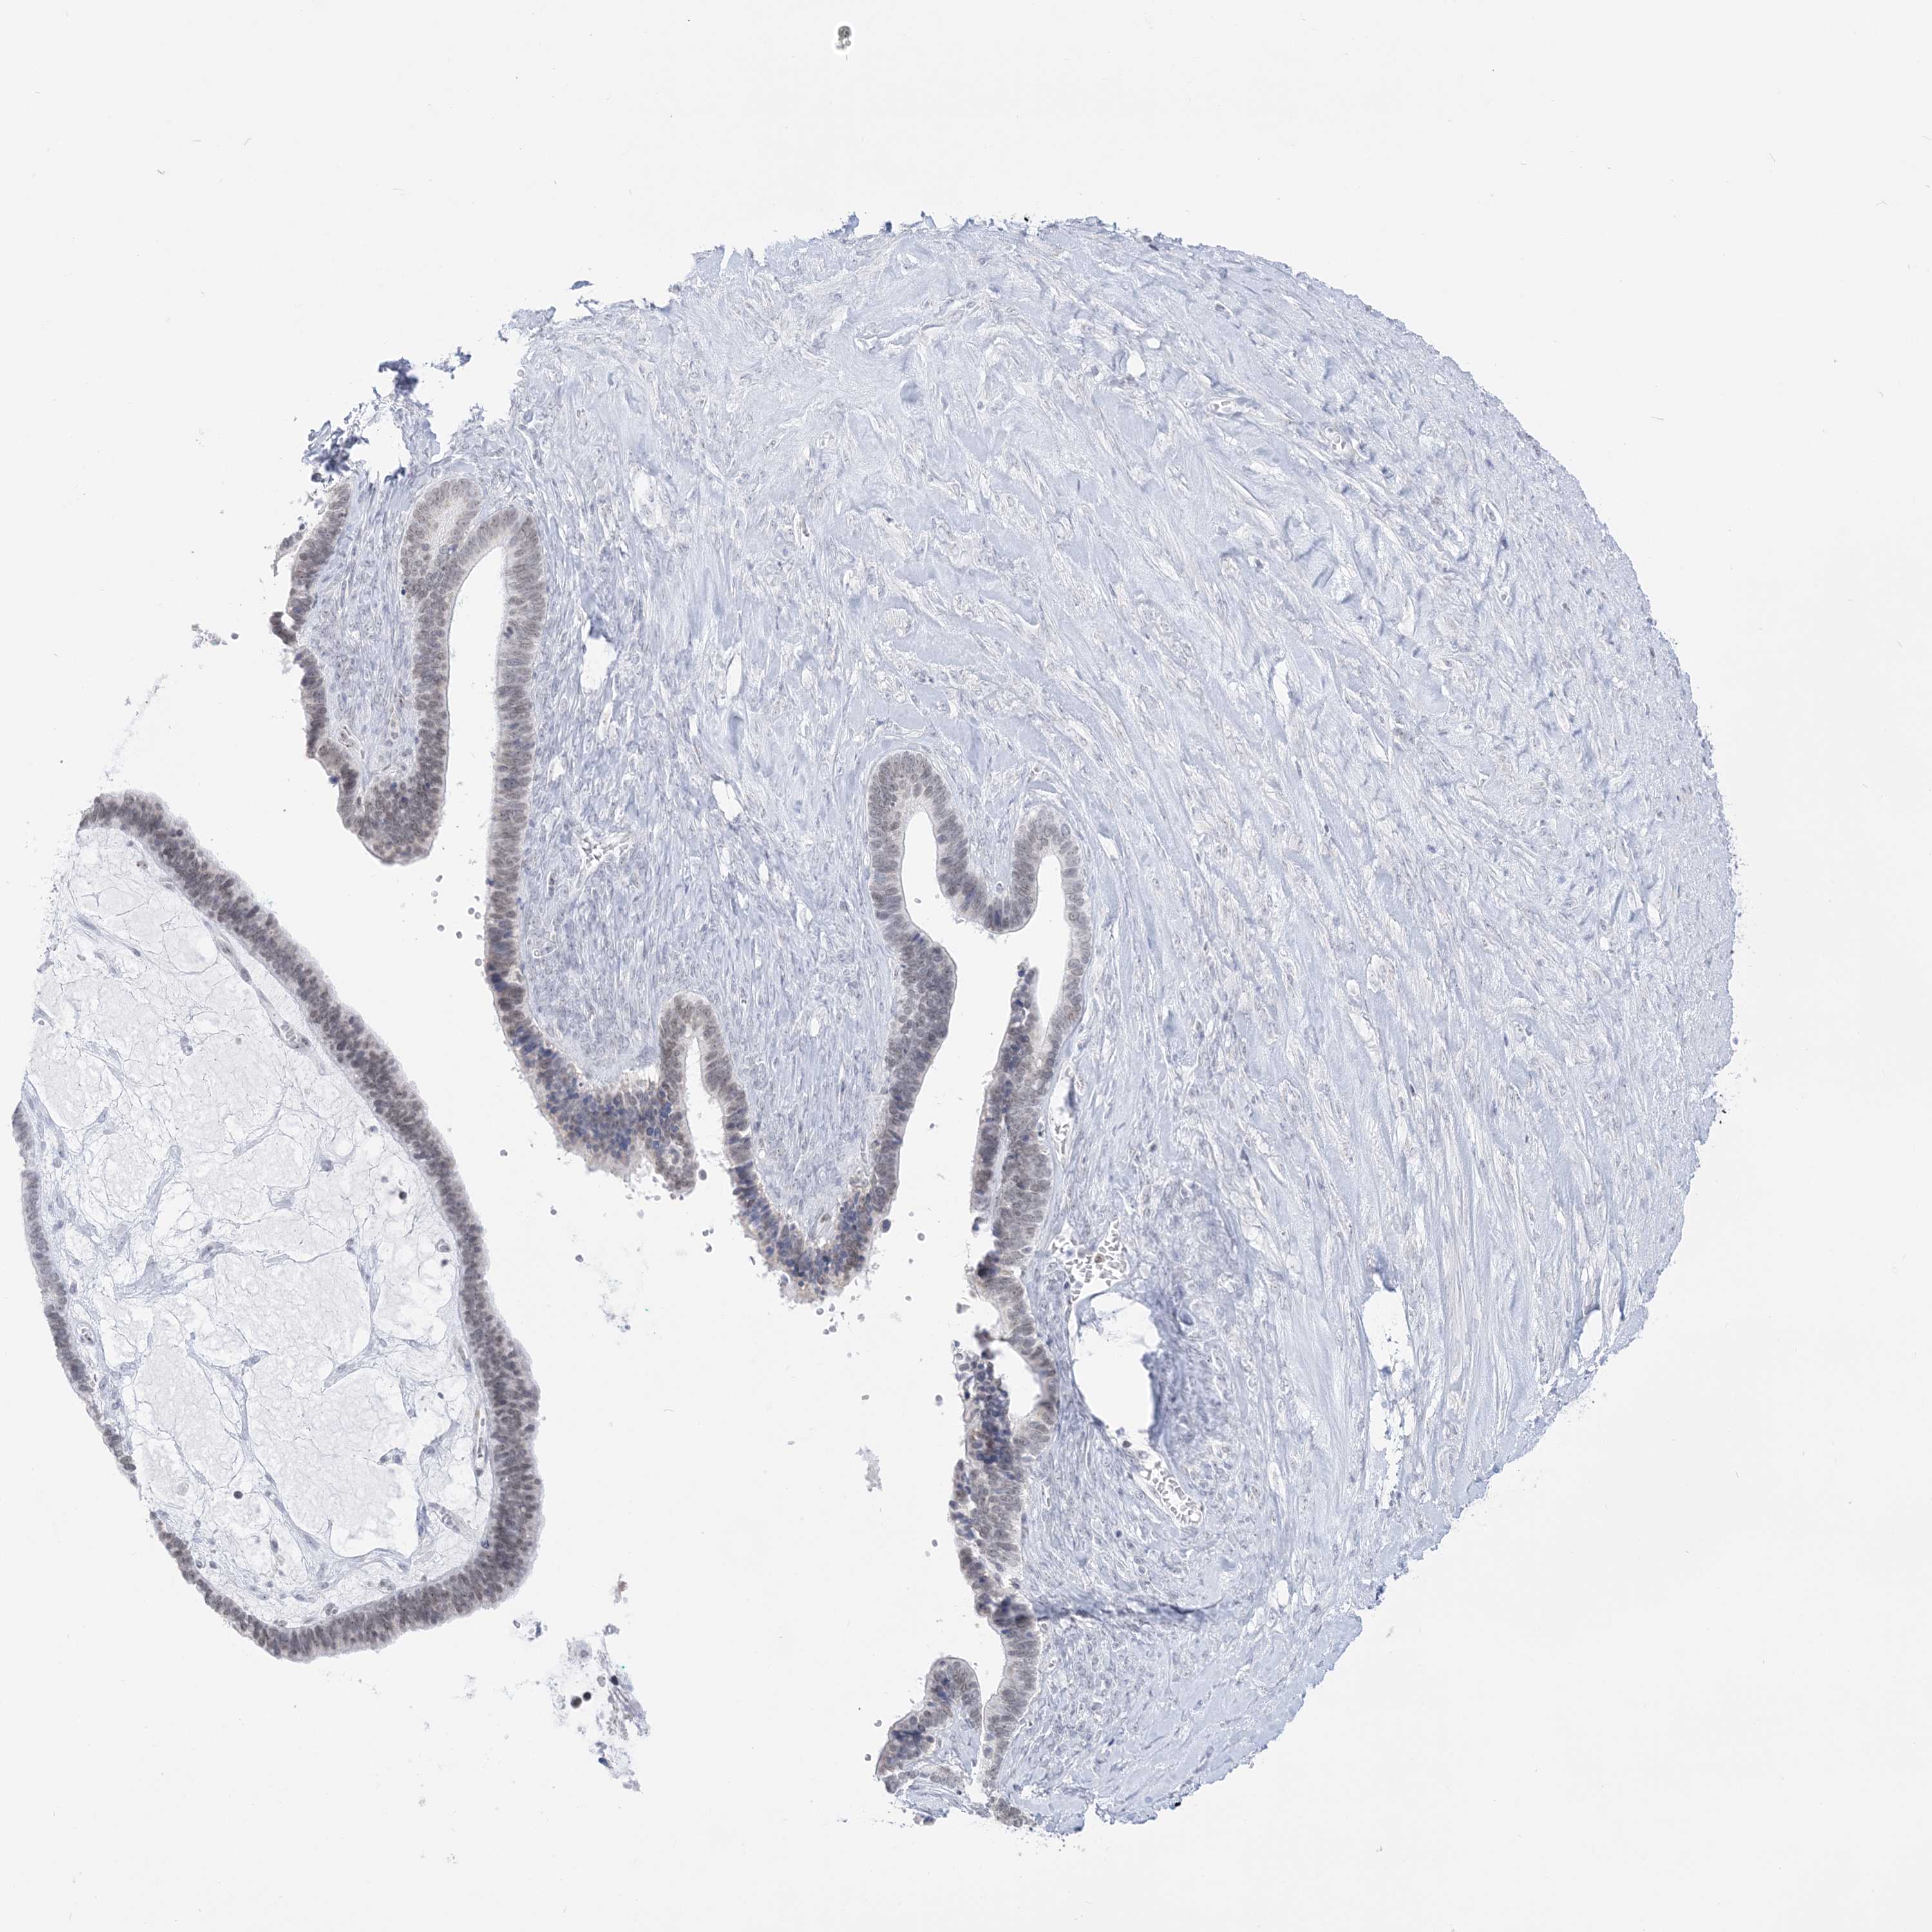

OVARIAN CANCER - Protein expressioni

A mouse-over function shows sample information and annotation data. Click on an image to view it in a full screen mode. Samples can be filtered based on level of antibody staining by selecting one or several of the following categories: high, medium, low and not detected. The assay and annotation is described here.

Note that samples used for immunohistochemistry by the Human Protein Atlas do not correspond to samples in the TCGA dataset.

Antibody stainingi

Antibody staining in the annotated cell types in the current human tissue is reported as not detected, low, medium, or high, based on conventional immunohistochemistry profiling in selected tissues. This score is based on the combination of the staining intensity and fraction of stained cells.

Each image is clickable and will lead to virtual microscopy that enables deeper exploration of all samples and also displays staining intensity scores, fraction scores and subcellular localization as well as patient and tissue information for each sample.

Antibody HPA036593

Cystadenocarcinoma, serous, NOS

Carcinoma, endometroid

Cystadenocarcinoma, mucinous, NOS

Carcinoma, NOS